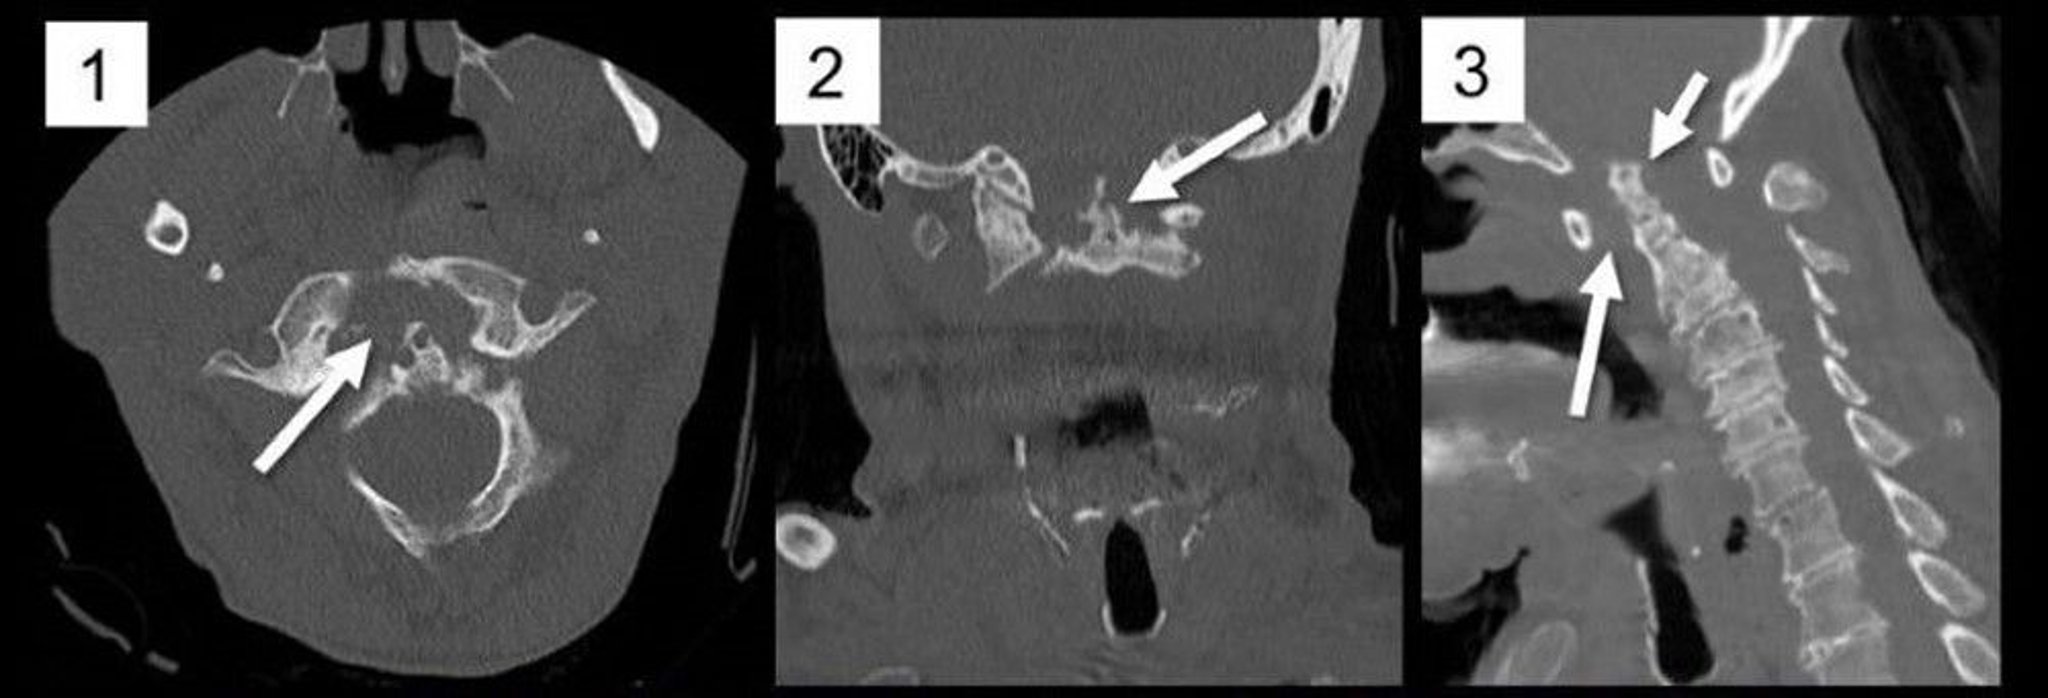

Atlantoaxial Subluxation (CT Scan)

Multiplanar reformations of a CT scan of the cervical spine in the axial (1), coronal (2), and sagittal (3) planes show marked widening of the anterior atlantodental interval (ADI) secondary to pannus formation as occurs in rheumatoid arthritis (RA) (1, arrow; 3, long arrow), causing posterior subluxation and basilar impression of the C2 odontoid process (3, short arrow). The odontoid process is markedly eroded (2, arrow), a typical finding in RA.

Image courtesy of A. John Tsiouris, MD.